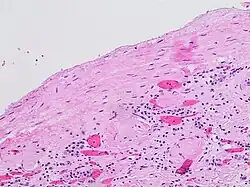

A renal cyst is a fluid collection in or on the kidney. There are several types based on the Bosniak classification. The majority are benign, simple cysts that can be monitored and not intervened upon. However, some are cancerous or are suspicious for cancer and are commonly removed in a surgical procedure called nephrectomy.

- Indeterminate cystic masses with thickened, irregular or smooth walls or septa with measurable enhancement. Approximately 40 to 60% of these lesions are ultimately found to be malignant, most commonly in the forms of cystic renal cell carcinoma and its multiloculated variant.[9][10][11] The remaining lesions are benign and include hemorrhagic cysts, chronic infected cysts, and multiloculated cystic nephromas.

- Malignant cystic masses with all the characteristics of category III lesions but also with enhancing soft tissue components independent of but adjacent to the septa. Approximately 85 to 100% of these lesions are malignant.[9][12]